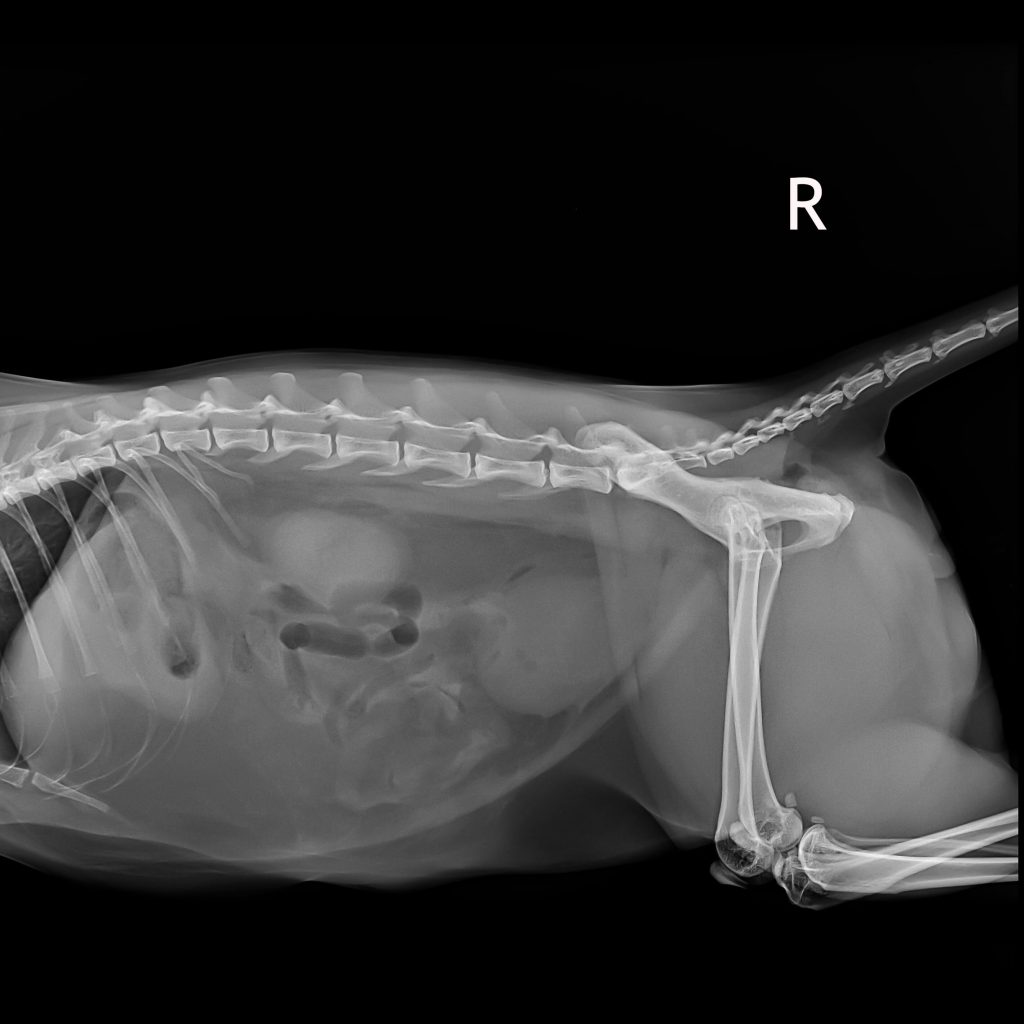

A bladder infection is diagnosed using a combination of physical examination, urine test and, if needed, imaging procedures. Your cat’s behaviour and symptoms often provide the first clues. A fresh urine sample is important to ensure a reliable diagnosis. Depending on the findings, your vet might do an ultrasound or take an X-ray if they suspect stones or a tumour. Getting an accurate diagnosis is essential for choosing the right treatment.

Ultrasound and other tests

If the cause remains unclear or the symptoms keep coming back, a vet might recommend imaging tests. For example, an ultrasound can be used to show urinary stones, tumours and changes in the bladder wall. X-rays can also help detect stones in the urinary tract. In rare cases, your vet might perform a cystoscopy to look directly at the bladder lining or to take small tissue samples.